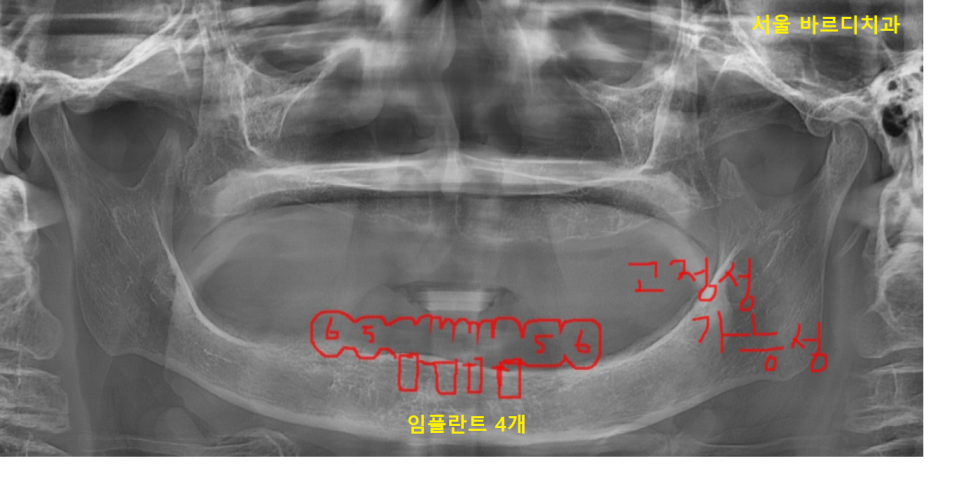

all on 4 (올온포)라 불리는 치료 방법입니다.

올온포 이름이 어렵죠~?

틀니를 끼지 않고

임플란트 4개만 심어 그 위에 머리를 올려

씹을 수 있게 해주는 방법입니다.

23.11.23

똑같이 임플란트를 심는데

(과정 동일)

브릿지 방식으로 머리를 만든다.

틀니가 필요 없다!

생각하시면 됩니다.